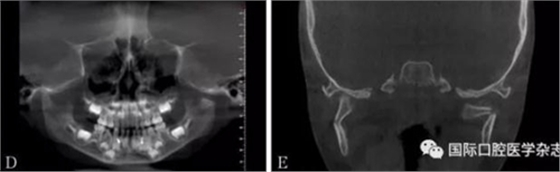

頜面部上下頜骨、顴骨及顴弓骨折、骨折片移位壓迫咀嚼肌群和下頜骨喙突,影響下頜骨的活動(dòng)而造成張口受限[10-12](圖 9、10)。

左:顴弓骨折CT平掃;右:顴弓骨折CT三維成像。

圖 10 顴弓骨折